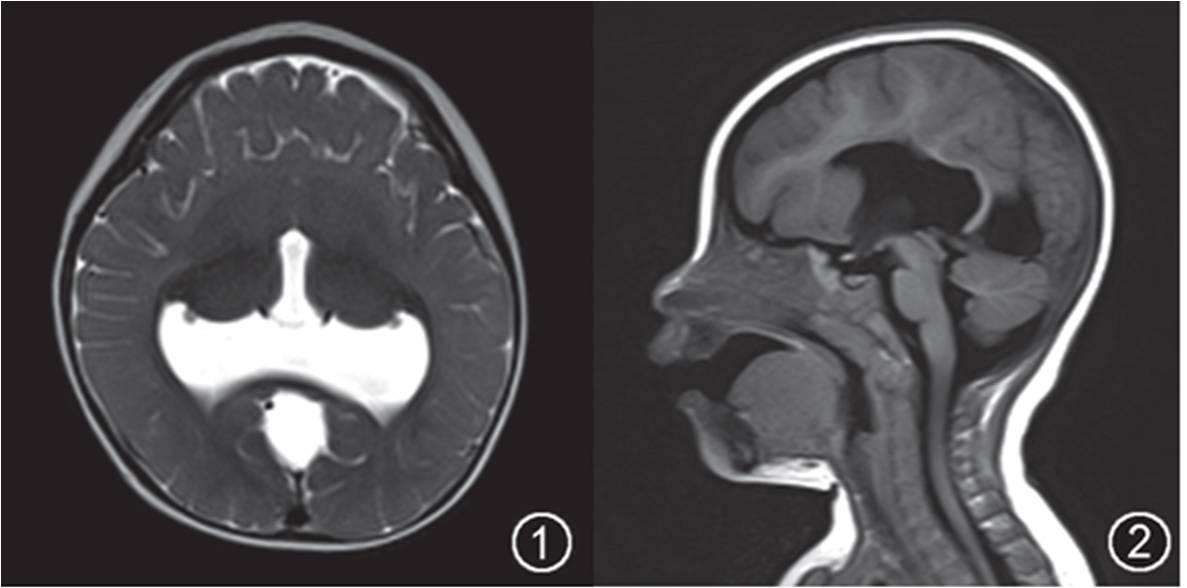

(二) 前腦無裂畸形(HPE):是由于孕程的第3~4周,前腦不能成功分裂端腦、間腦。按照疾病嚴(yán)重程度由高到低將HPE分為4型:無腦葉型、半腦葉型、腦葉型和半球中央變異型HPE。

女,10個月,半腦葉型前腦無裂(HPE)。軸面T2WI(圖1)示大腦半球前部縱裂缺如,雙側(cè)額葉融合伴發(fā)育不良,兩側(cè)豆?fàn)詈思拔矤詈瞬糠秩诤希瑐?cè)腦室前角未發(fā)育、后角融合,伴發(fā)背側(cè)間裂小囊腫及小頭畸形。矢狀面T1WI(圖2)示胼胝體膝部及體部缺如。